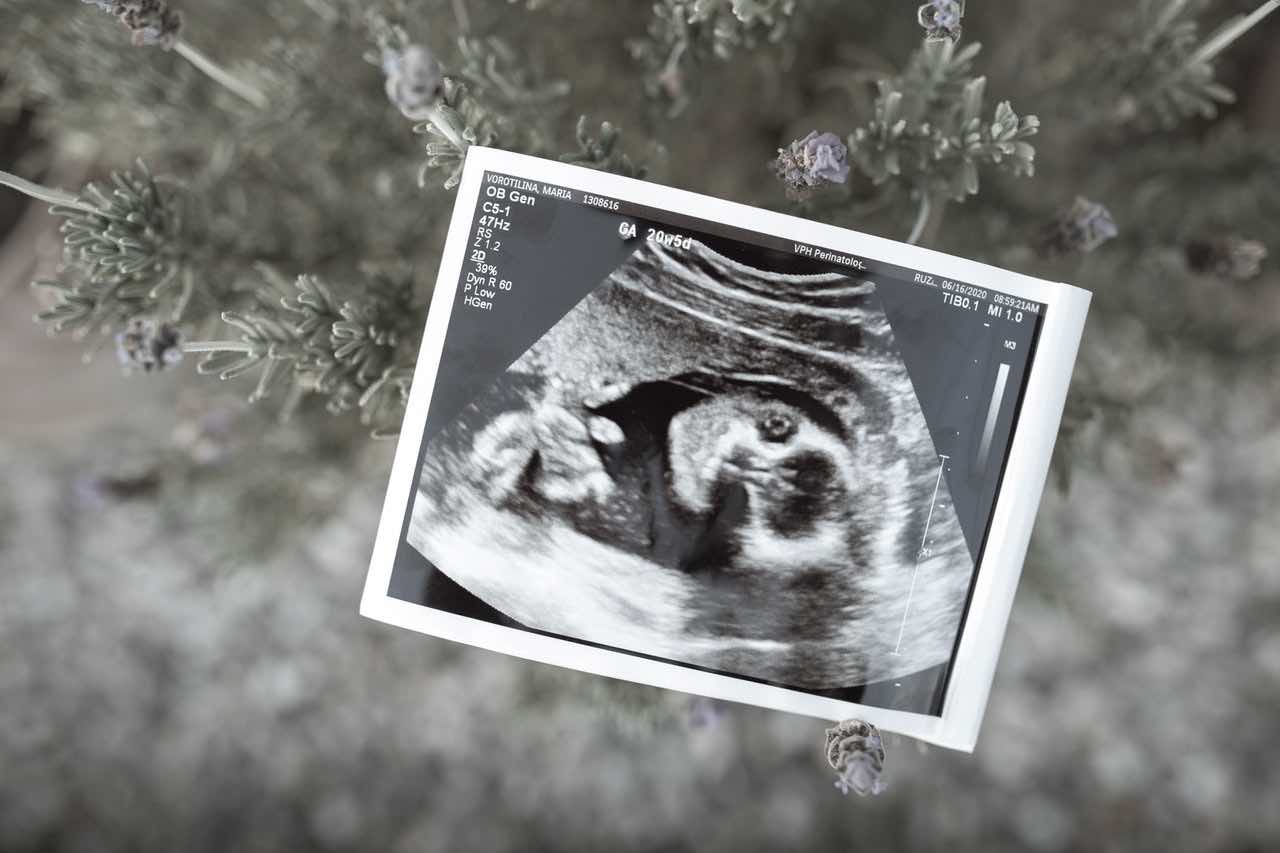

הדרך לאבחן מומי לב עוד ברחם היא באמצעות בדיקת על קול (אולטרסאונד). כבר בין השבוע ה-16 וה-20 להריון. בנוסף, על הרופאים לדעת לחפש נוכחות של אוושה (רשרוש) בלב, שיכולה לרמוז לפגם מבני.

סקירת מערכות נועדה לגלות מומי לב. למעשה, כבר בבדיקת שקיפות עורפית ניתן לקבל רמזים למום בלב. אפשר וצריך לגלות פגם במחיצה בין העליות (ASD), בין החדרים (VSD), או פגם החלפה של העורקים הגדולים. ראה חוזר משרד הבריאות בעניין